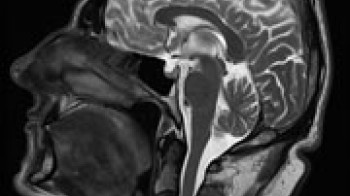

MRI mozga / glavobolje, upale , tumori, drugo

MRI pregled mozga je najbolja metoda za analizu mozga, njegove bijele I sive mase, bilo da se radi o upalnim, tumorskim, autoimunim ili drugim stanjima. Nema štetnog jonizujućeg zračenja a nezamjenjiva je metoda za dijagnostiku sekundarnih glavobolja, odnosno oboljenja koja uzrokuju glavobolje. Zajedno sa MRA-magnetnom angiografijom-pregledom krvnih žila mozga- dobija se vrhunsko slikovno stanje endokranijuma.